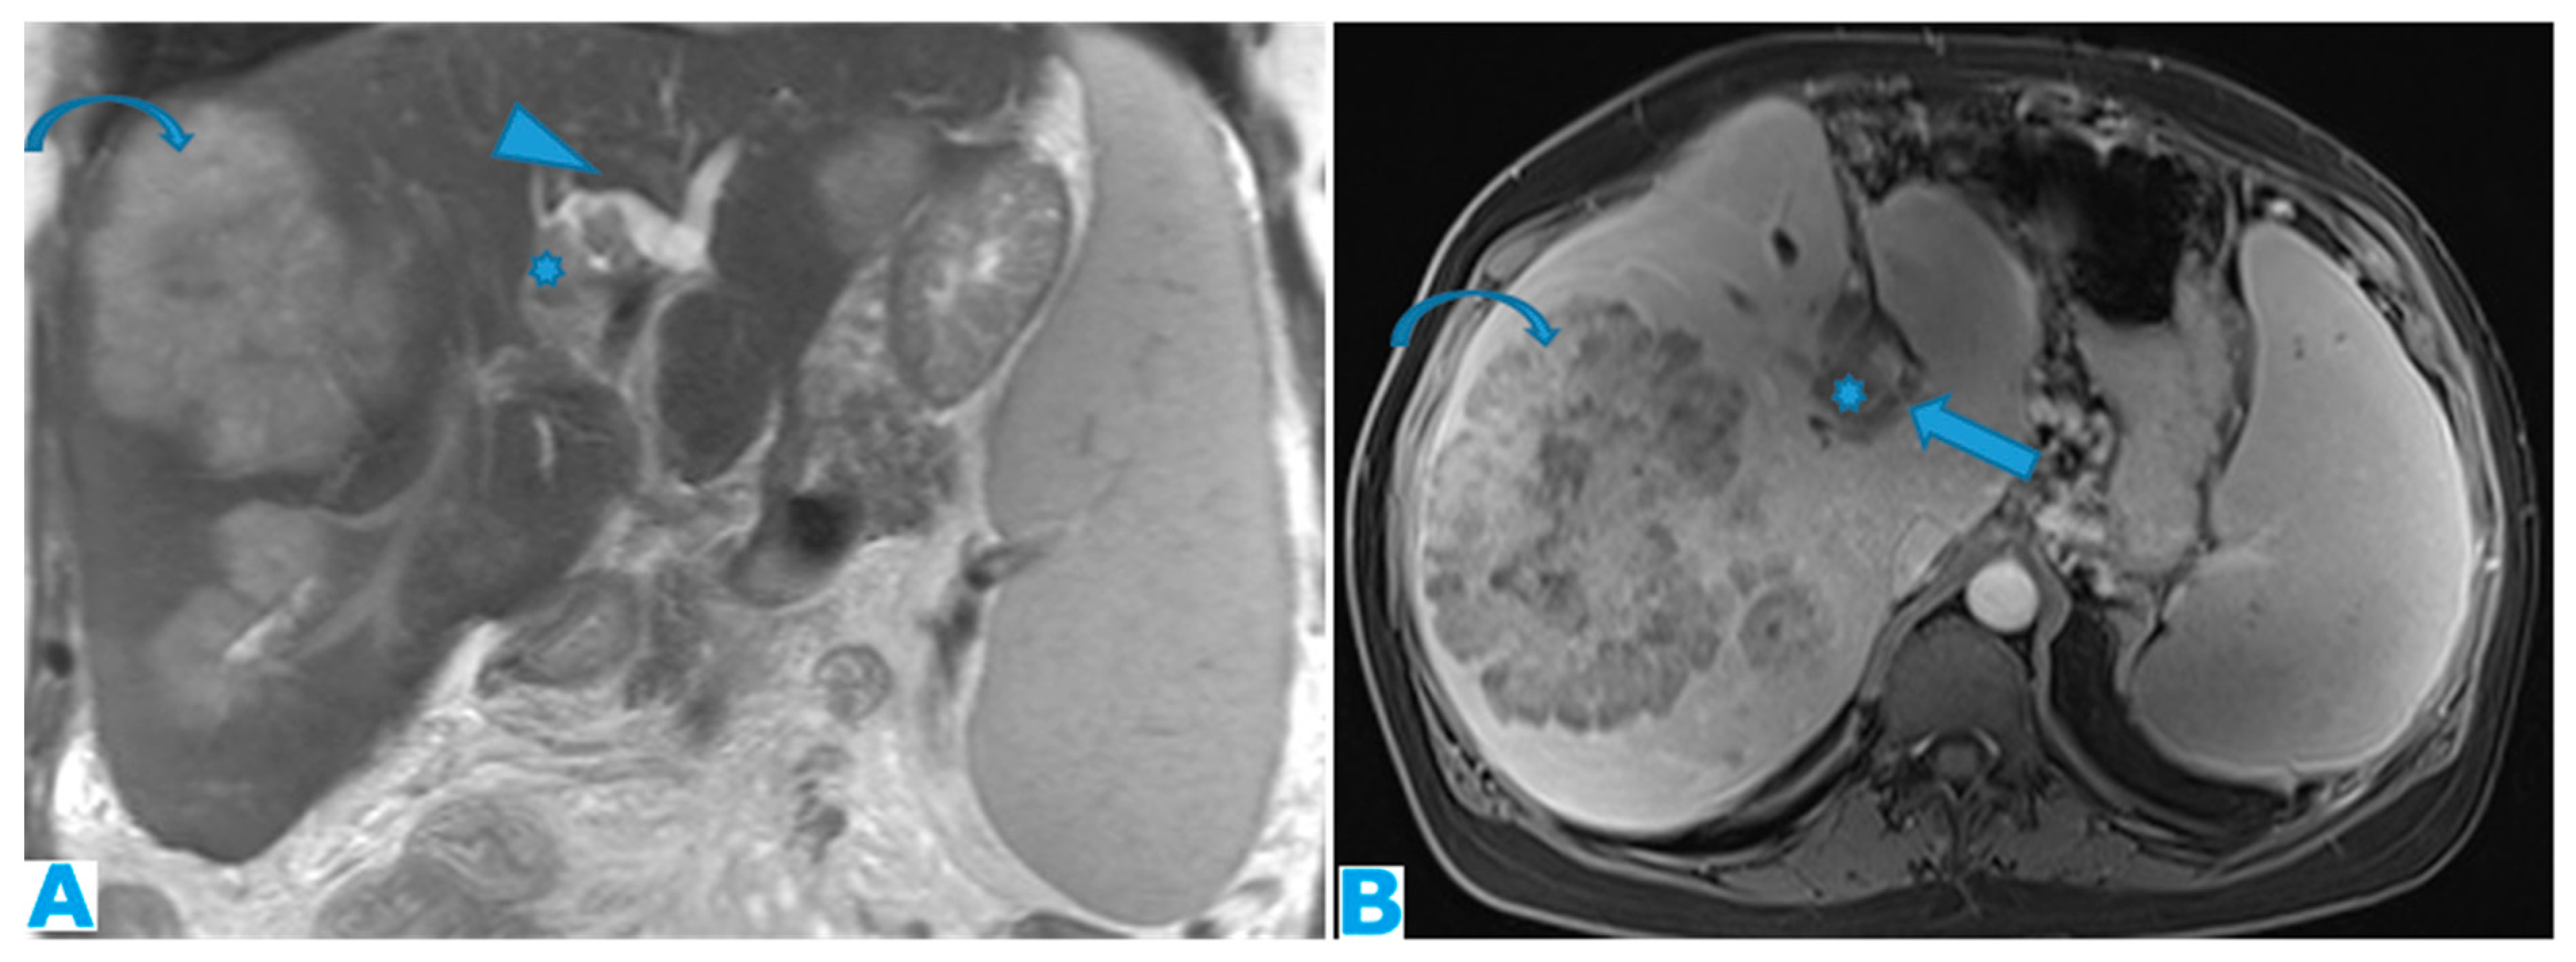

Figure 13.

Coronal T2WI (A), axial CE portal phase FST1WI (B). PC from colon adenocarcinoma: periportal deposit (*) that causes segmental intrahepatic biliary dilatation (arrowhead) and portal vein compression (arrow). The patient had a known portal hypertension due to massive hepatic metastases (curved arrow) and splenomegaly.